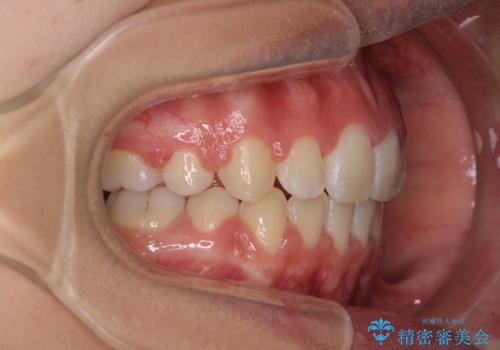

くちばしのように突出した前歯 口元を下げる抜歯矯正

- 上下の出っ歯を気にして来院された患者様です。

口元を積極的に引っ込めるために、上下左右の第一小臼歯を4本抜歯することとしました。

前歯部の突出と開咬は、舌突出癖によるものでしたので、舌のトレーニングをしっかりと行っていただき、1年半程度と短期間で治療を終えることができました。